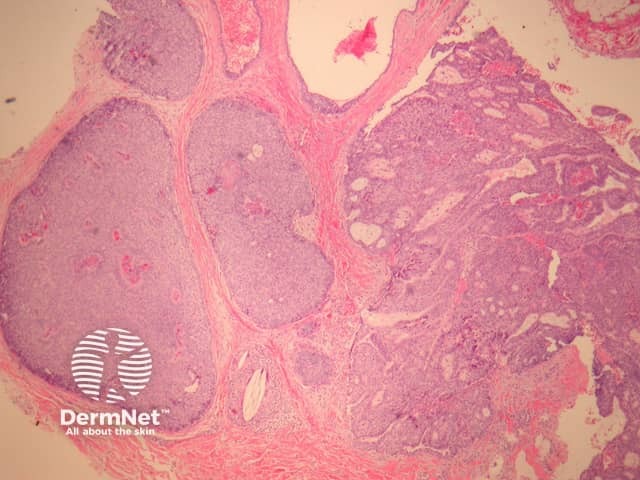

In EMPSGC, sections show a dermally based tumour mass under an intact epidermis. It consisted predominantly of nodules of the tumour as well as cystic spaces somewhat reminiscent of a hydrocystoma (figures 1, 2, 3). Higher power reveals a uniform population of round-to-oval cells with fairly abundant pale and pink cytoplasm. The nuclei have fine stippled chromatin consistent with neuroendocrine differentiation (figure 4). Areas transitioning into mucinous carcinoma, with tumour islands floating in copious mucinous material may be seen (figure 5).

Figure 1

Figure 2